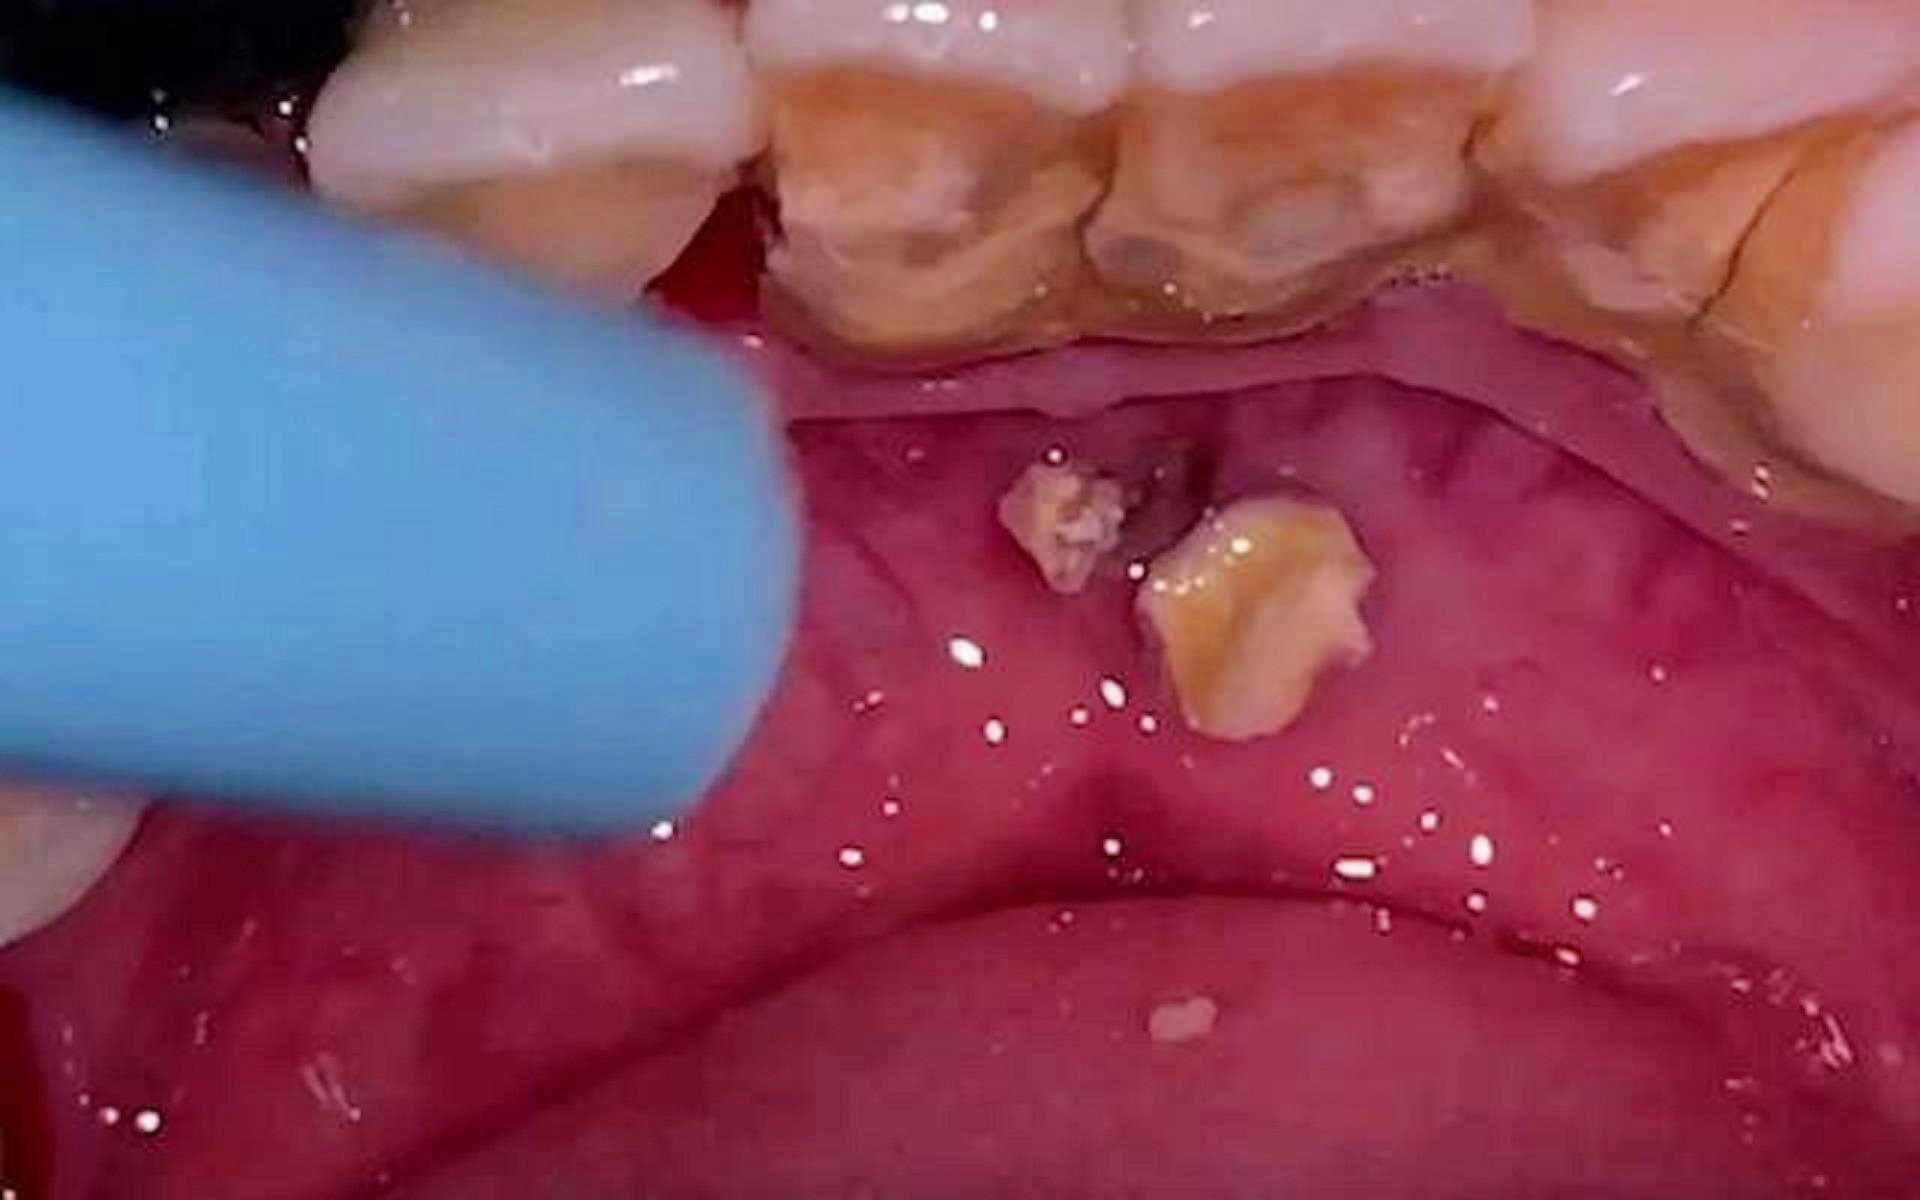

牙結(jié)石是牙齒表面沉積的硬結(jié)物質(zhì),主要由牙菌斑和礦物質(zhì)組成,牙結(jié)石形成的原因包括口腔衛(wèi)生不良、飲食習(xí)慣、牙齒結(jié)構(gòu)等,牙結(jié)石不僅影響牙齒美觀,還可能導(dǎo)致牙齦炎、牙周病等口腔問題,保持口腔清潔,預(yù)防牙結(jié)石的形成至關(guān)重要。

近年來,市場上出現(xiàn)了一些聲稱能在短時間內(nèi)(如5秒)脫落牙結(jié)石的產(chǎn)品和方法,這些方法主要包括使用特定的化學(xué)制劑或通過高頻振動等方式來清除牙結(jié)石,這些方法的真實效果及其安全性尚待驗證。

對于聲稱能在短時間內(nèi)清除牙結(jié)石的方法,我們需要了解其原理,某些化學(xué)制劑可能通過溶解牙結(jié)石中的礦物質(zhì)來達(dá)到清除效果,而高頻振動可能通過震動牙結(jié)石,使其松動脫落,這些方法可能對牙齒和口腔組織造成刺激或損傷,尤其是化學(xué)制劑,如果使用不當(dāng),可能導(dǎo)致牙齒敏感、牙齦灼傷等問題。